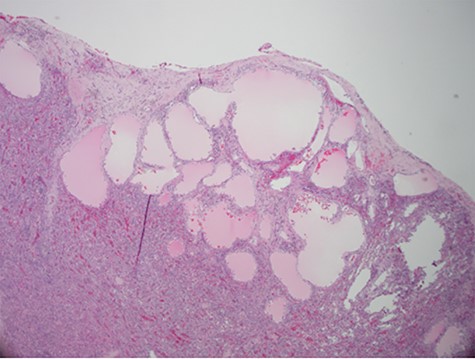

Despite aggressive resuscitation, the patient’s hemodynamics and clinical exam declined. He was taken emergently to the operating room for exploratory laparotomy, evacuation of hemoperitoneum and splenectomy. The spleen was noted to have an isolated nodular, cystic appearing portion in addition to large area of capsular tear. In total, he received four units of PRBC, four units of fresh frozen plasma and one unit of platelets peri-operatively; however, he continued to show signs of hemorrhagic shock. Morning lab-work revealed a Hgb of 5.9 mg/dL from 7.6 mg/dL despite two additional units of PRBC on post-operative day one. Due to continued decline in Hgb and ongoing tachycardia, he returned to the operating room on post-operative days two and four for repeat exploration. Each procedure failed to identify an obvious source of bleeding, except for diffuse oozing in the peritoneal cavity. Further family discussion revealed a history of Hemophilia A in the patient’s brother, diagnosed during childhood. New diagnostic workup was obtained and was consistent with a variant of Hemophilia A. He was subsequently treated with recombinant Factor VIII to a goal of 80–100%, per hematology recommendations, and underwent definitive closure with hemostasis noted on post-operative day six. Pathology report returned as a ruptured spleen with hemorrhage and a subcapsular nodule with dilated lymphovasculature consistent with splenic lymphangioma (Figs 2 and 3).

Hematoxylin and eosin stain photomicrographs from splenectomy consistent with splenic lymphangioma with 40x magnification.

Isolated splenic lymphangiomas are most often an incidental radiologic finding, as most are asymptomatic [2, 3]. CT typically shows single or multiple low density, thin walled, sharply marginated subcapsular cyst(s) [2]. There is no contrast enhancement and the presence of curvilinear, peripheral mural calcifications is further supportive of a cystic lymphangioma [2]. Differential diagnosis may include hemangioma, epidermoid cyst, mesothelial cyst and parasitic or hydatid cysts; with histopathologic examination required for definitive diagnosis [1–4]. Histologic analysis often consists of a single layer of flattened endothelium lined spaces, filled with eosinophilic proteinaceous material instead of blood as in a hemangioma [2].